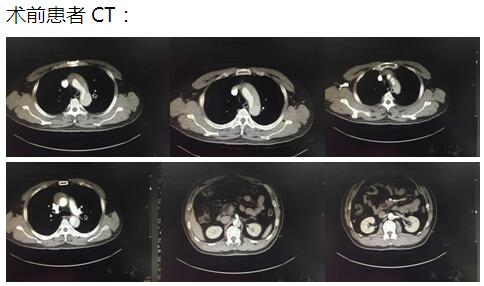

患者是一位48歲中年男性,因胸痛1小時(shí)入院,我院CT提示主動(dòng)脈夾層累及胸、腹主動(dòng)脈全層,診斷為主動(dòng)脈夾層(D ebaKey I型)?;颊卟∏槲V兀中g(shù)治療是挽救其生命的唯一希望。為了挽救病人生命,經(jīng)過麻醉科、手術(shù)室、體外循環(huán)組的術(shù)前充分討論,心胸外科廖金文主任、廖承輝副主任帶領(lǐng)團(tuán)隊(duì)決定為其施行復(fù)雜而高難度的淺低溫停循環(huán)下“孫氏手術(shù)”。術(shù)中見主動(dòng)脈全程及三分支受累,右冠受累,冠脈開口受壓狹窄,予以行“升主動(dòng)脈 主動(dòng)脈弓置換 降主動(dòng)脈術(shù)中支架置入術(shù)”,團(tuán)隊(duì)成員歷經(jīng)約10個(gè)小時(shí)的奮戰(zhàn),手術(shù)順利完成。術(shù)后六小時(shí)患者意識(shí)完全清醒,現(xiàn)在已完全康復(fù)。